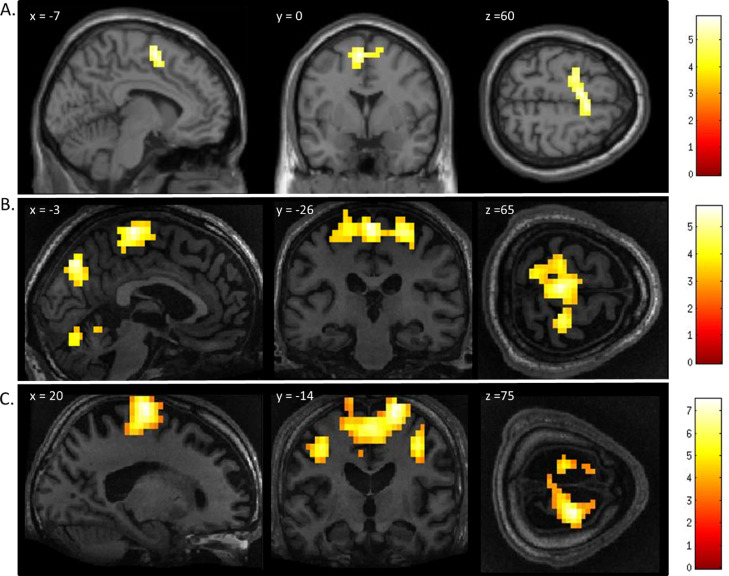

The motor imagery task elicited significant activation in the supplementary motor area and primary motor cortex for both patients and healthy controls (Fig. 1 and Table 1). Additionally, the signal intensity changes observed in the motor imagery task in both patients was within the normal ranges of responses found in the healthy volunteers (Fig. 2A)

Fig. 1.

FMRI activation observed during the motor imagery task for a group of healthy participants (A) and two completely locked-in GBS patients (B and C). A. In healthy participants, a whole-brain group analysis revealed significant activation in the supplementary motor area, using a threshold of p < .05, FDR-corrected for multiple comparisons. Group analysis is shown on a canonical single-subject T1 MRI image. B and C. In both patients, extensive significant activation was observed in the supplementary and primary motor cortex. Patients’ results are displayed at a peak voxelwise threshold p < .001, uncorrected followed by whole-brain FDR-corrected for significance using cluster extent, p < .05 and displayed on their individual normalized T1 image.

In healthy volunteers, the spatial navigation task elicited significant activation in the occipito-parietal junction, cerebellum, parahippocampal gyrus (PPA), and left middle frontal gyrus (Fig. 3A). Previous studies have reported the most reliable activity across participants is found within the occipito-parietal junction as opposed to PPA. Fernandez-Espejo et al. (2014) found activity in 142/14 volunteers within the OPJ as opposed to 8/12 participants with activity within the PPA. Activity within this area during spatial navigation has been previously used for successful communication in patients with disorders of consciousness (Fernández-Espejo & Owen, 2013). In this study, significant activation of the occipito-parietal junction was also observed in both patients during the spatial navigation task (Fig. 3B and C and Table 1). For both patients, we examined the signal intensity changes in OPJ against those of the healthy volunteers and both patients were within the normal ranges of responses for the healthy volunteers. found in the healthy volunteers (Fig. 2B).

Fig. 3.

FMRI activation observed during the spatial navigation imagery task for a group of healthy participants (A) and two completely locked-in GBS patients (B and C). (A) In healthy participants, a whole-brain group analysis revealed significant activation in the occipito-parietal junction, cerebellum, parahippocampal gyrus, and left middle frontal gyrus using a threshold of p < .05, FDR-corrected for multiple comparisons. Group analysis is shown on a canonical single-subject T1 MRI image. (B) In patient 1 a whole-brain analysis revealed significant activation in the occipito-parietal junction with results displayed at a peak voxelwise threshold p < .001, uncorrected followed by whole-brain FDR-corrected for significance using cluster extent, p < .05 and displayed on the patient's normalized T1 image. (C) Patient 2 had weaker activation in the occipito-parietal junction with results displayed at a peak voxelwise threshold of p < .001, uncorrected for multiple comparisons for visualization.